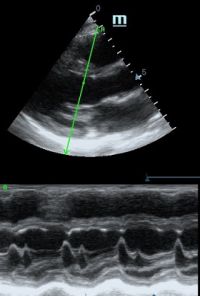

Но как же провести стандартные измерения в М-режиме, если мы его не использовали? На помощь приходит функция Free Xros M – анатомический М-режим. Имея записанную в память прибора видео петлю, мы можем провести линию М-режима в любом месте, при этом корректируя изначально не оптимальный угол.

Возможности применения функции многогранны: от измерения толщины стенок левого желудочка, движения створок митрального клапана и кооптации нижней полой вены до оценки сократимости миокарда как глобально, так и по сегментам.

Показатели УЗ сканирования в М-режиме

Какие показатели можно использовать при анатомическом М-режиме помимо привычных срезов через конец створок митрального клапана или синуса Вальсальве?